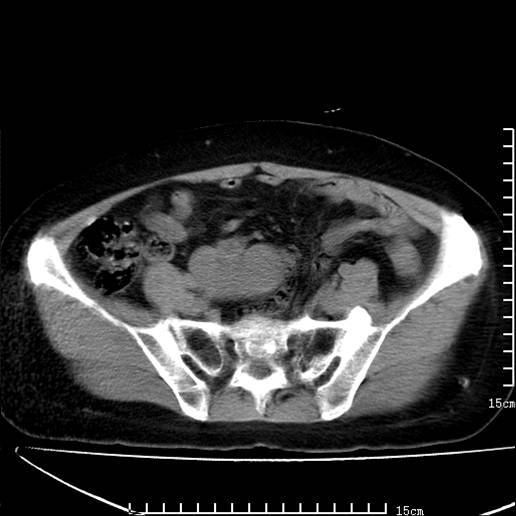

以下是引用pujunzhi在2008-5-30 15:31:00的发言:[br]异位肾—盆腔肾。当看到肾窝无肾脏时,要想到孤立肾和异位肾,异位肾最常见是盆腔肾,偶见胸腔,易误认为肺占位,只要想到就不会漏诊。建议增强扫描。